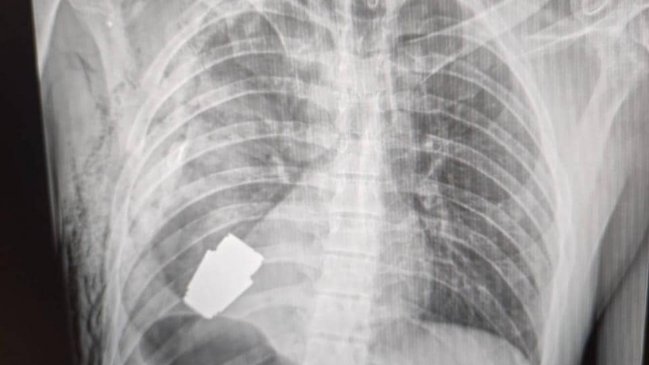

Médicos extrajeron una granada sin explotar del pecho de un soldado ucraniano

La cirugía se realizó en presencia de dos zapadores que velaban por la seguridad de los profesionales de salud.

Médicos de las Fuerzas Armadas de Ucrania